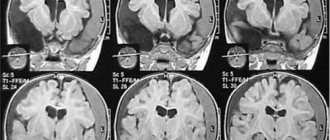

При необходимости проводится хирургическое вмешательство, в ходе которого удаляются внутримозговые и оболочечные гематомы, восстанавливается нарушенный кровоток.

Последствия ушиба головы

Последствия сильных ударов по голове кулаком нередко проявляются в виде интракраниального кровотечения, отека мозговой ткани, дислокации мозговых структур, что в итоге может привести к инвалидности или летальному исходу.